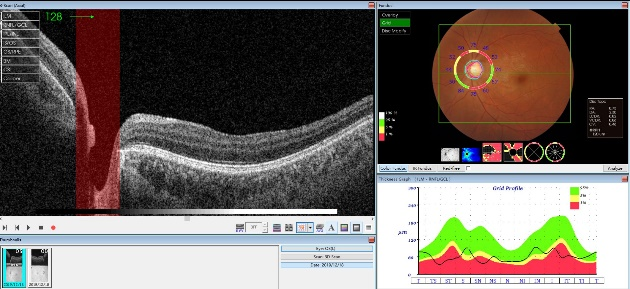

青光眼患者的视神经OCT扫描

青光眼视神经诊断的三要素为:

◎ 盘沿丢失;

◎ 视网膜神经纤维层缺损;

◎ 视盘线状出血。

当只有一项要素改变时,需要结合视野或其他视神经检查综合判断。